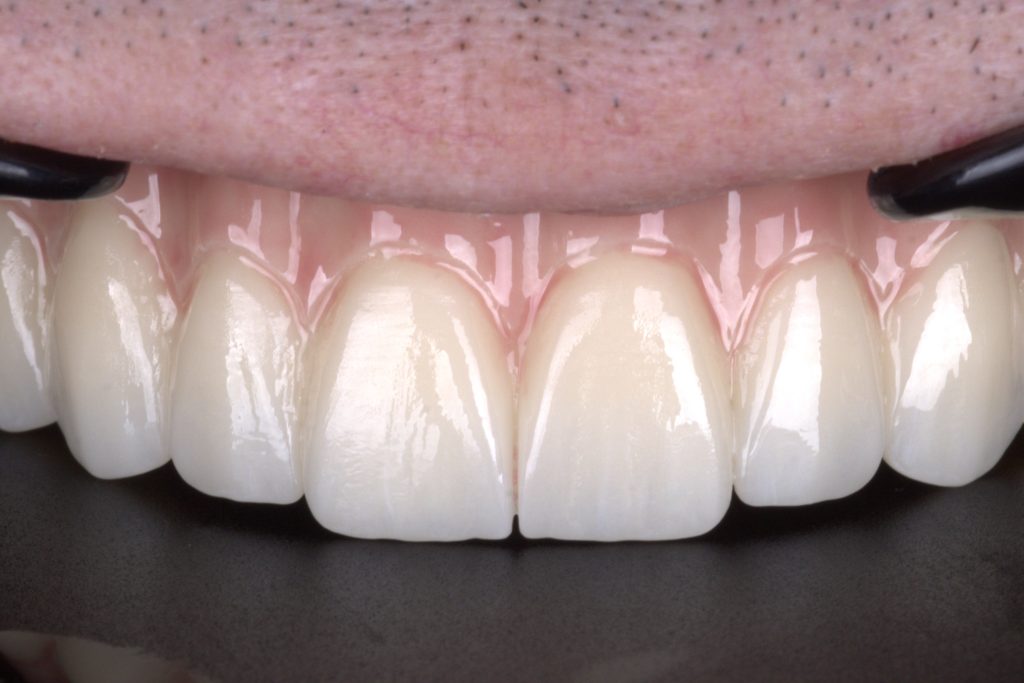

Exquisite incisal edges and perfect occlusion in full-contour zirconia.

I just cant resist a closer look at these exquisite incisal edges